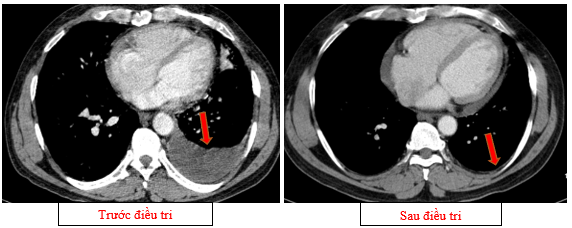

-         Chụp cắt lớp vi tính ổ bụng (11/2025): Nhu mô gan phải có vài nốt, nốt lớn nhất hạ phân thùy VII có nốt giảm tỷ trọng, ngấm thuốc kém sau tiêm đường kính 8mm, hạ phân thùy II, III có nốt giảm tỷ trọng đường kính (tổn thương giảm đáng kể so với phim chụp ngày 08/2025). Các ổ đặc xương rải rác đốt sống ngực thắt lưng, xương cùng và xương chậu hai bên.

Hình 11: Tổn thương ngấm thuốc kém nhu mô gan hạ phân thùy II giảm đáng kể kích thước

Hình 12: Tổn thương ngấm thuốc kém nhu mô gan hạ phân thùy VII giảm đáng kể kích thước

+      Các tổn thương ngấm thuốc kém do di căn tại gan giảm kích thước đáng kể (27mm còn 8mm)